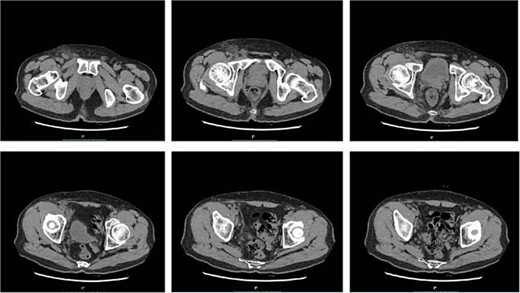

A follow-up complete blood count was normal and C-reactive protein 21.8 mg/L, PCT 0.09 ng/ml. CT re-examination indicated that the right inguinal lymph nodes had decreased in size (Fig. 6). Subsequently, the prednisone dosage was reduced by 5 mg every 7 days until discontinuation, with no further fever symptoms reported.